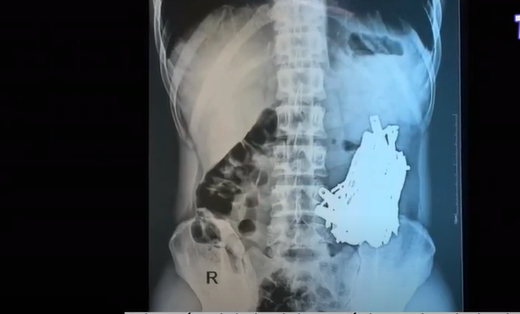

Cứu sống bệnh nhân nuốt hơn 1kg đinh vít. Ngày 1/10, các bác sĩ ở Litva cho biết họ đã lấy ra hơn 1kg đinh vít từ dạ dày của một bệnh nhân nam.

Theo các bác sĩ, người đàn ông này đã bắt đầu nuốt các vật nhỏ bằng kim loại sau khi cai rượu. Bệnh nhân nhập viện ở thành phố cảng Klaipeda trong tình trạng bụng nặng và rất đau đớn.

Những hình ảnh chụp X-quang dạ dày của bệnh nhân cho thấy nhiều mảnh kim loại, trong đó một số có chiều dài lên đến 10cm.